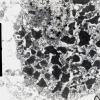

Neuronal Ceroid Lipofuscinosis (NCL) (6)